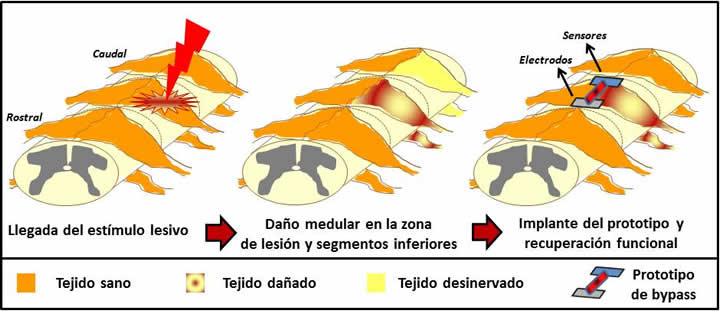

A pesar de que el objetivo final es la fabricación de un prototipo que actúe como bypass activo local en la médula espinal y que éste sea capaz de restablecer la transmisión de señales eléctricas, el esfuerzo de estas profesionales va encaminado en un primer momento en “aprender más cosas del daño medular, comprender mejor lo que le pasa a los pacientes con este tipo de lesión y que estos dispositivos nos den información que no tenemos”.

Las doctoras Serrano y López Dolado explican que su trabajo consistirá en poner en contacto los distintos nanomateriales y dispositivos integrados de mayor complejidad con células del sistema nervioso central. Este procesos se realizará inicialmente in vitro, en placas de cultivo. Si las respuestas son positivas, indican estas profesionales, la idea es que en fases más avanzadas se implante en un modelo experimental de lesión medular en ratas.

Antes de ello, en el cuarto bloque, la Escuela Internacional Superior de Estudios Avanzados de Trieste, en Italia, se encargará del estudio funcional de los dispositivos y del prototipo elaborado en modelos in vitro in vivo mediante el empleo de técnicas electrofisiológicas. Además, tanto en el bloque tres como el cuatro participará la quinta institución, la empresa alemana Mfd-Diagnostics GmbH.